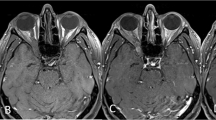

This study aims to identify radiologically the position of the optic foramen in relation to the anterior face of the sphenoid sinus, to aid surgeons in their planning for orbital decompression.

CT scans of 100 orbits from 50 adult patients without any abnormality were assessed. Primary outcome measures included: position and measurement of the distance from the optic foramen to the anterior face of the sphenoid sinus. Secondary outcomes included: medial orbital wall length, distance from the optic foramen and the anterior face of the sphenoid sinus to the carotid prominence in the sphenoid sinus, and the thickness of bone anterior to the optic foramen.

The mean location of the optic foramen was just posterior to the position of the anterior face of sphenoid sinus, with an average distance of +0.4 +/− 3.5 mm. In 54% of orbits the optic foramen was positioned posterior to the anterior face of the sphenoid sinus. The finding was symmetrical in 80% of patients.

Our study identifies that the optic foramen lies posterior to the anterior face of sphenoid sinus in approximately half of cases. The position may be asymmetric in 20% of individuals.